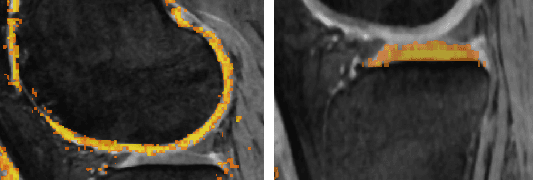

Abstract:State-of-the-art automated segmentation algorithms are not 100\% accurate especially when segmenting difficult to interpret datasets like those with severe osteoarthritis (OA). We present a novel interactive method called just-enough interaction (JEI), which adds a fast correction step to the automated layered optimal graph segmentation of multiple objects and surfaces (LOGISMOS). After LOGISMOS segmentation in knee MRI, the JEI user interaction does not modify boundary surfaces of the bones and cartilages directly. Local costs of underlying graph nodes are modified instead and the graph is re-optimized, providing globally optimal corrected results. Significant performance improvement ($p \ll 0.001$) was observed when comparing JEI-corrected results to the automated. The algorithm was extended from 3D JEI to longitudinal multi-3D (4D) JEI allowing simultaneous visualization and interaction of multiple-time points of the same patient.

Abstract:We present a fully automated learning-based approach for segmenting knee cartilage in the presence of osteoarthritis (OA). The algorithm employs a hierarchical set of two random forest classifiers. The first is a neighborhood approximation forest, the output probability map of which is utilized as a feature set for the second random forest (RF) classifier. The output probabilities of the hierarchical approach are used as cost functions in a Layered Optimal Graph Segmentation of Multiple Objects and Surfaces (LOGISMOS). In this work, we highlight a novel post-processing interaction called just-enough interaction (JEI) which enables quick and accurate generation of a large set of training examples. Disjoint sets of 15 and 13 subjects were used for training and tested on another disjoint set of 53 knee datasets. All images were acquired using a double echo steady state (DESS) MRI sequence and are from the osteoarthritis initiative (OAI) database. Segmentation performance using the learning-based cost function showed significant reduction in segmentation errors ($p< 0.05$) in comparison with conventional gradient-based cost functions.

Abstract:A fully automated knee MRI segmentation method to study osteoarthritis (OA) was developed using a novel hierarchical set of random forests (RF) classifiers to learn the appearance of cartilage regions and their boundaries. A neighborhood approximation forest is used first to provide contextual feature to the second-level RF classifier that also considers local features and produces location-specific costs for the layered optimal graph image segmentation of multiple objects and surfaces (LOGISMOS) framework. Double echo steady state (DESS) MRIs used in this work originated from the Osteoarthritis Initiative (OAI) study. Trained on 34 MRIs with varying degrees of OA, the performance of the learning-based method tested on 108 MRIs showed a significant reduction in segmentation errors (\emph{p}$<$0.05) compared with the conventional gradient-based and single-stage RF-learned costs. The 3D LOGISMOS was extended to longitudinal-3D (4D) to simultaneously segment multiple follow-up visits of the same patient. As such, data from all time-points of the temporal sequence contribute information to a single optimal solution that utilizes both spatial 3D and temporal contexts. 4D LOGISMOS validation on 108 MRIs from baseline and 12 month follow-up scans of 54 patients showed a significant reduction in segmentation errors (\emph{p}$<$0.01) compared to 3D. Finally, the potential of 4D LOGISMOS was further explored on the same 54 patients using 5 annual follow-up scans demonstrating a significant improvement of measuring cartilage thickness (\emph{p}$<$0.01) compared to the sequential 3D approach.